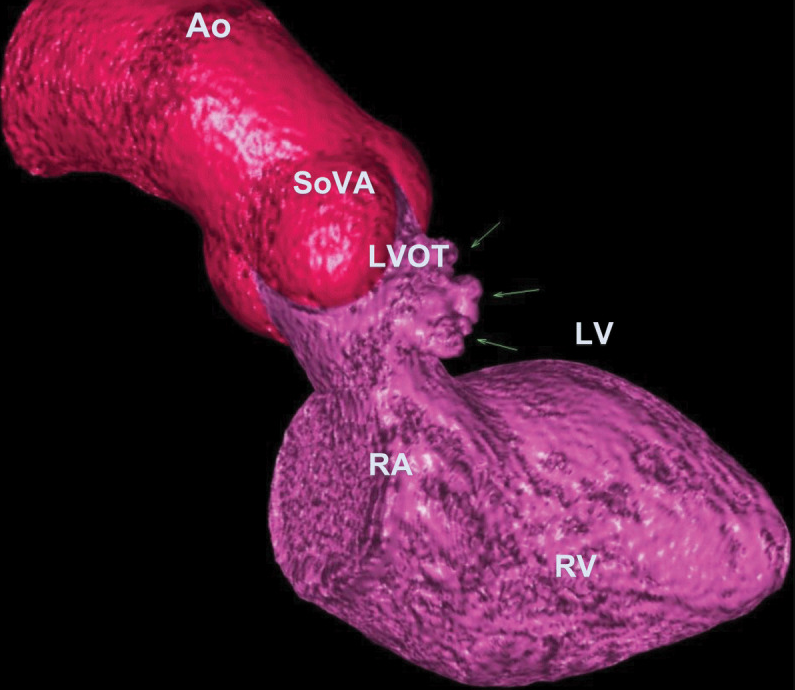

值得注意的是,发现了一个16mm宽颈的风袋状室间隔膨出瘤,同时存在卵圆孔未闭和左向右分流(图1,图2)。

图1. 三维心脏CTA显示室间隔膨出瘤(箭头所示)。

AO(主动脉);SoVA(瓦氏窦);LVOT(左心室流出道);LV(左心室);RA(右心房);RV(右心室)